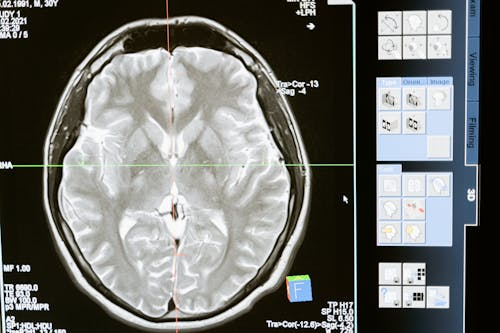

2️⃣ MRI(자기 공명영상)

→ 뇌경색 초기 병변까지 정밀하게 확인 가능